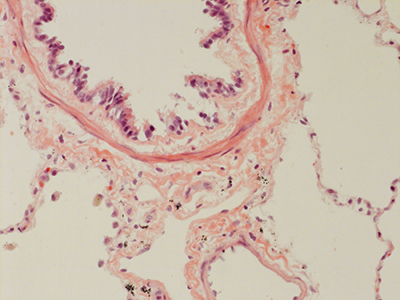

31 Year Old Adult Human Lung D0036 H&E